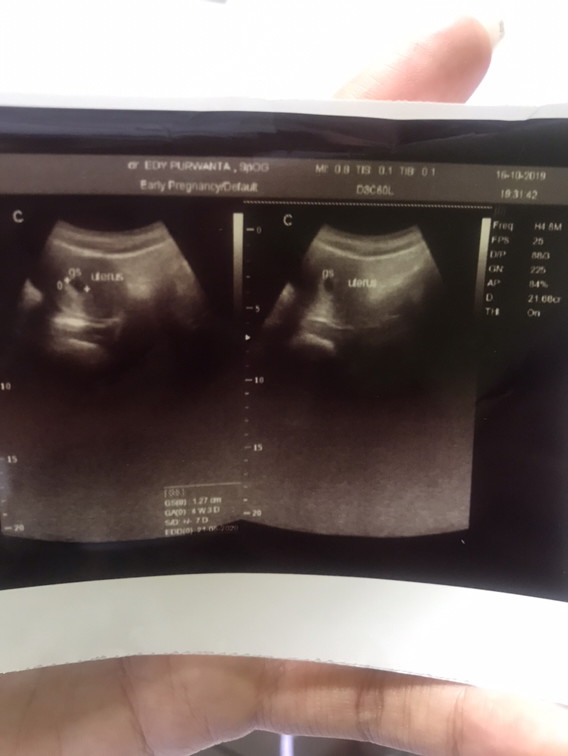

Ada yg pernah gak? Klo dihitung dri hpht misalkan usia kehamilannya 5minggu 6hari tpi pas usg masih 5minggu 4 hari kayak gtu,beda duahari? Ini hasil usg aku brusan, kata dokternya sih bru kantong doang yg kelihatan,jdi dsuruh blik lagi 2 minggu kemudian, ada yg pernah usg 5 minggu dh kelihatan janinnya?